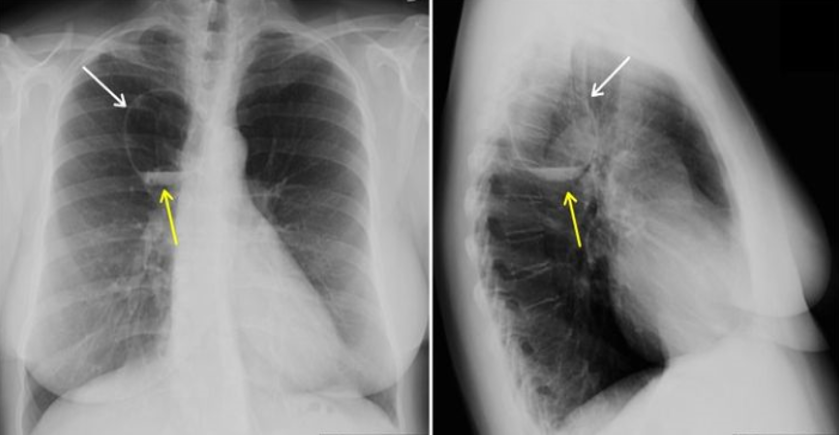

What is this x-ray showing?

What 3 findings suggest this?

Right Tension Pneumothorax w/

Left Tension Pneumothorax

Flattening of left diaphragm

Deviated to the right

Left pneumothorax